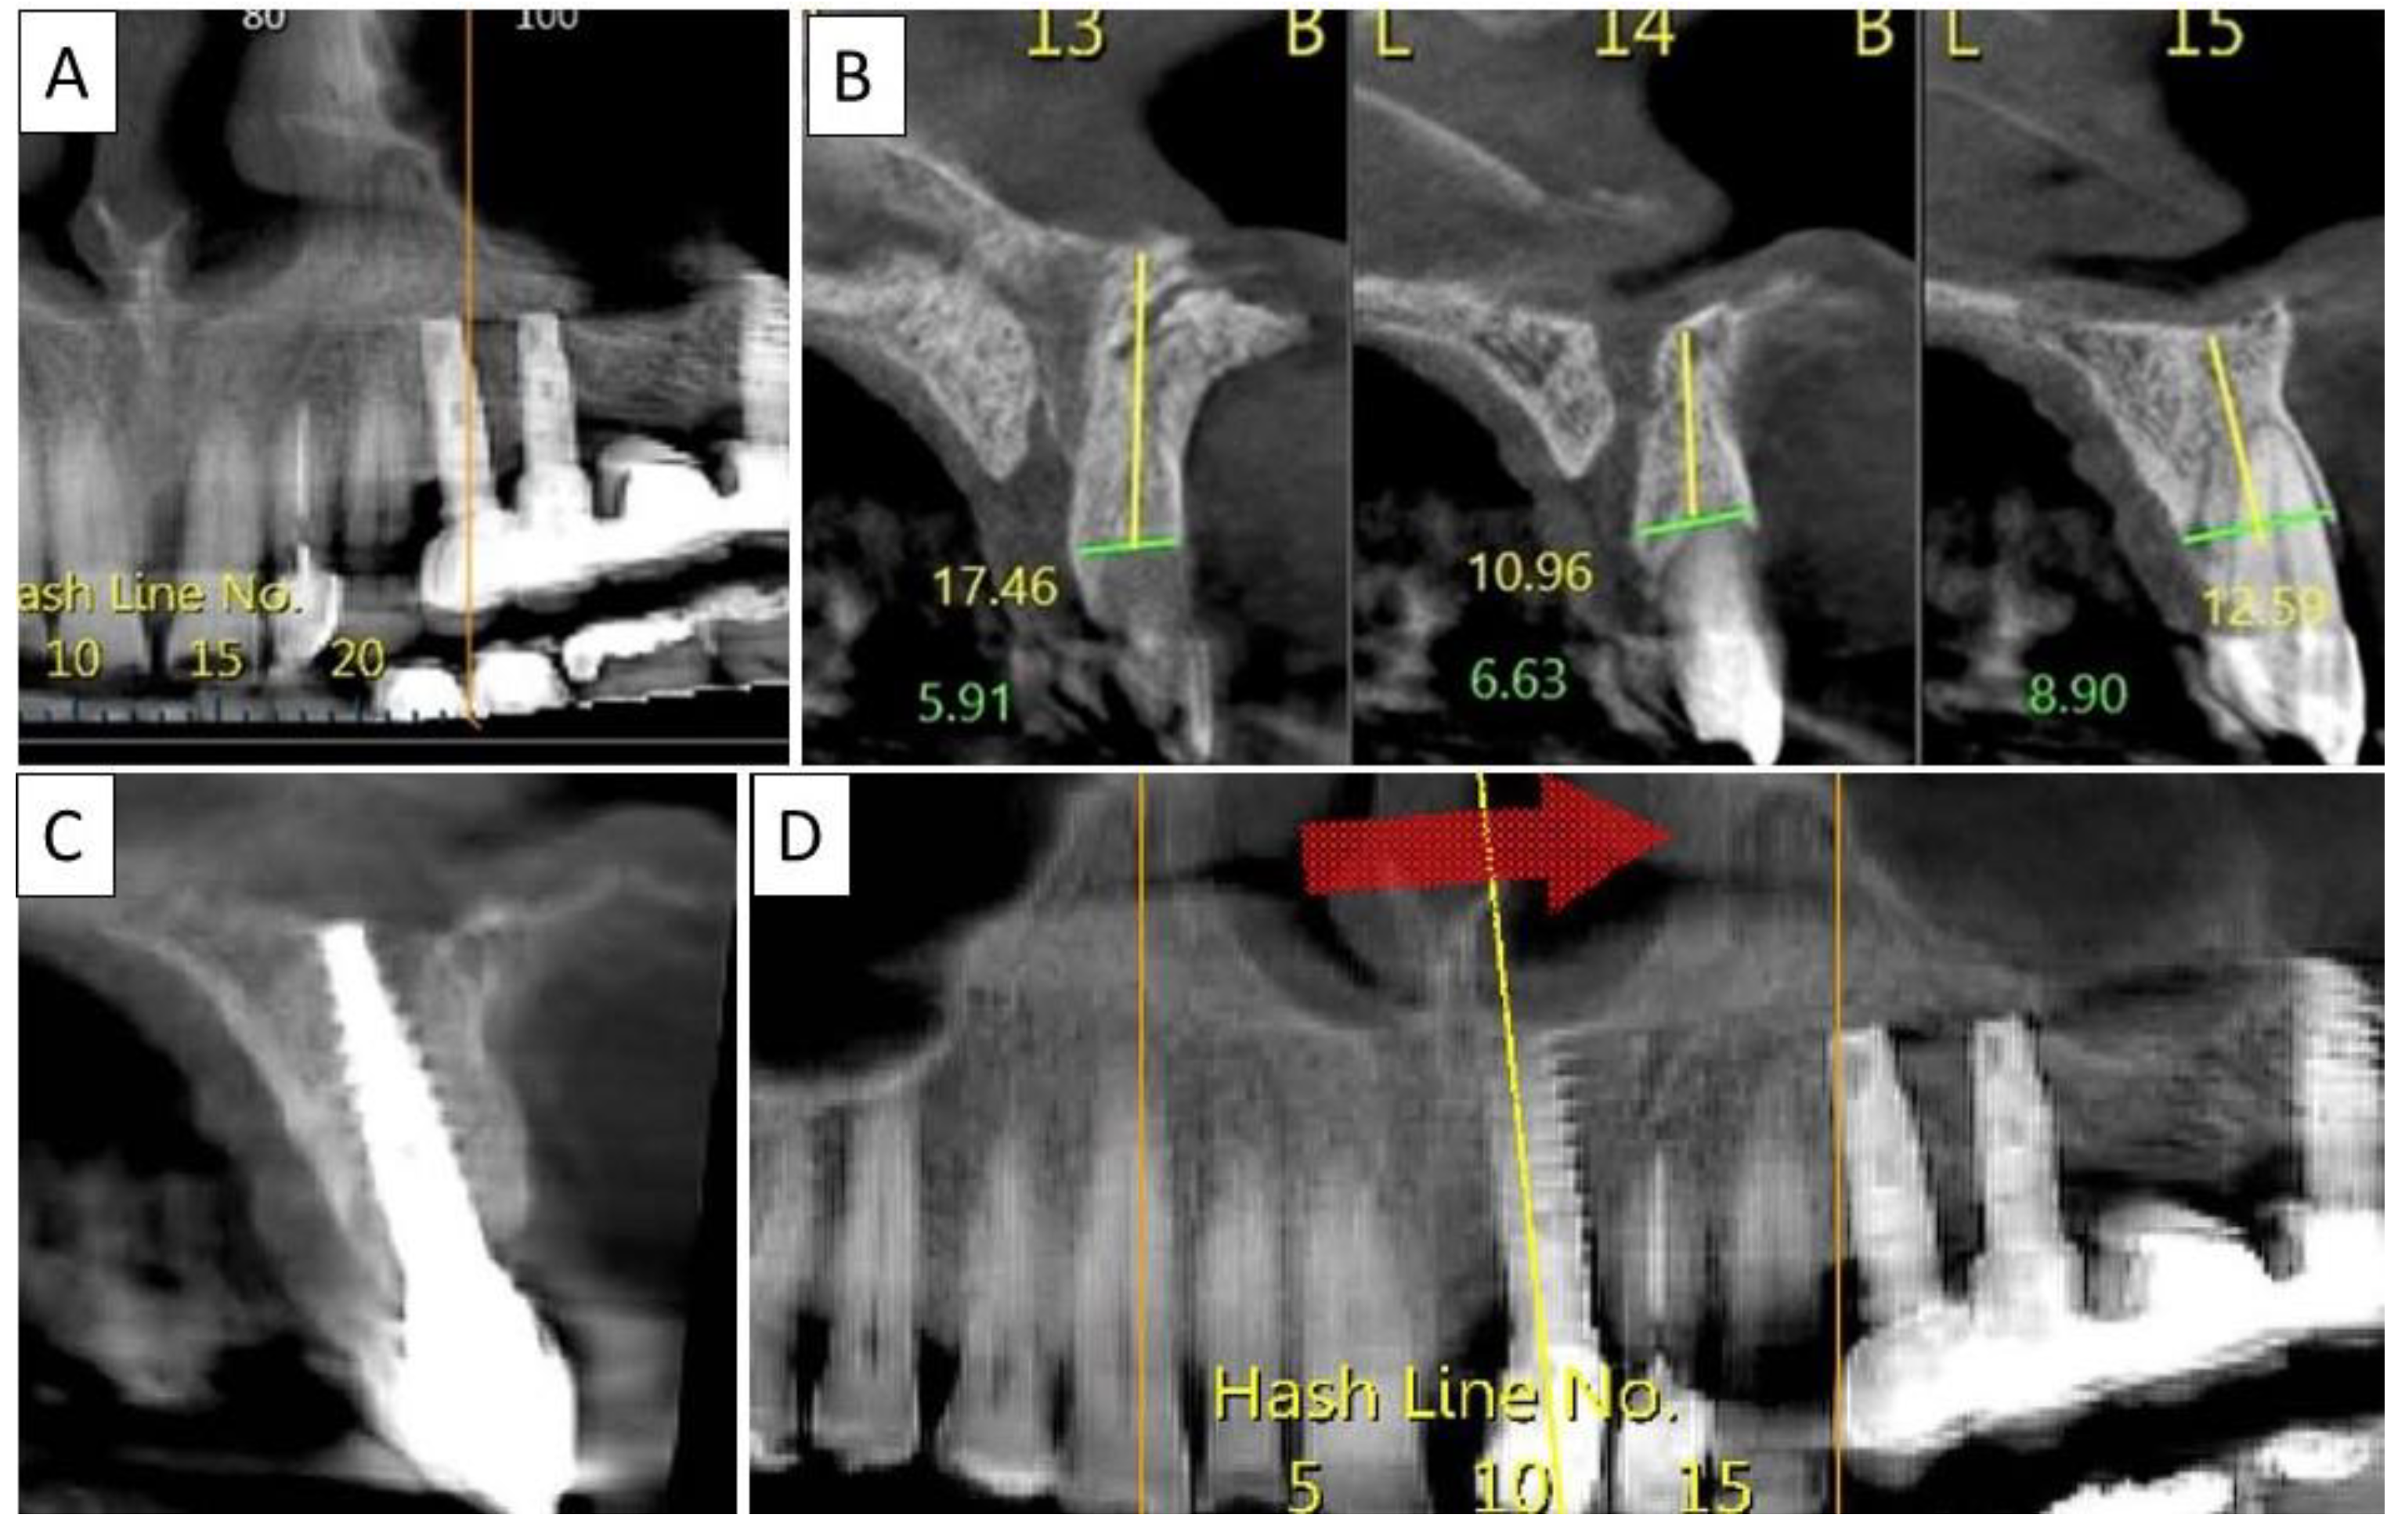

3.4. Case 4

A 60-year-old female patient in good general health condition. Patient presented with tooth 15, root canal treatment, post core and PFM crown and vertical root fracture with associated severe bone loss including loss of buccal cortical plate. Palatal cortical plate was intact.

Nontraumatic extraction of tooth 15 (Figure 8), followed by bone augmentation using the magnesium membrane shield technique to rebuild the buccal wall as described in Section 2.

Figure 8.

(A,B) Alveolar socket following atraumatic extraction and curettage. Severe bone loss on buccal wall. (C) Buccal wall was created using the magnesium membrane shield technique. (D) Application of allograft. (E) Closing sutures and immediate provision. (F) Four months post operatively there was a regeneration of bone defect, including fully regenerated cortical bone. The implant was stable and there was a good healing of the soft tissues. The black arrow indicates the position of the magnesium membrane.

Four months post operatively, there was an excellent regeneration of bone defect including a fully regenerated cortical buccal plate (Figure 9). The implant was stable and there was a good healing of the soft tissues.

Figure 9.

(A) Panoramic CBCT section shows associated apical radiolucency of tooth 15. (B) Coronal CBCT section shows tooth 15 with vertical root fracture and destroyed buccal bony wall and intact palatine. (C) Panoramic CBCT section shows bone formation around the implant in area 15. The coronal CBCT section shows the implant placed in the region of tooth 15.